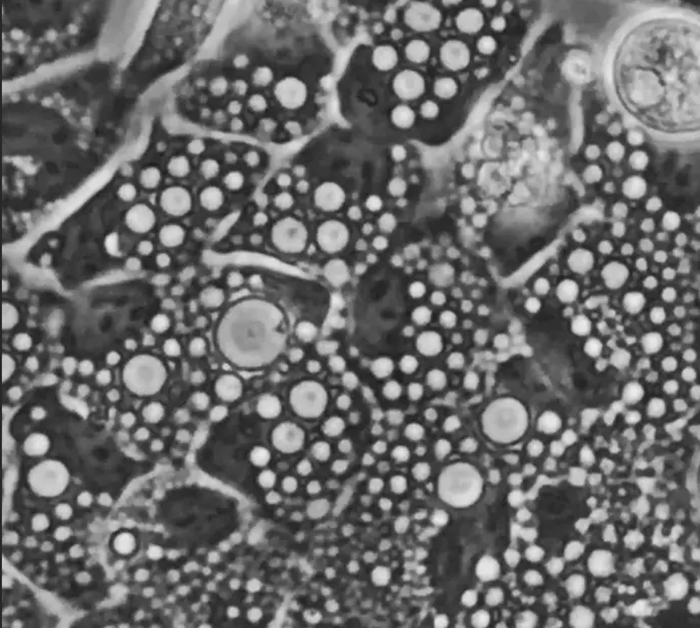

画像:リソソーム由来の数十個の円形液胞を示す顕微鏡画像。 (Credit:Jay Xiaojun Tan Lab)

私たちの細胞の中には、「リソソーム」と呼ばれる、細胞内の廃棄物処理システムとして機能する小さな器官が存在します。このシステムが正常に働くことは、細胞の健康、さらには私たちの健康的な老化に不可欠です。しかし、ストレスがかかると、このリソソームが異常に膨れ上がり、水風船のようになることがあります。この「リソソームの空胞化」と呼ばれる現象は、多くの疾患と関連していることが知られています。

研究チームは、細胞がリソソームの空胞化を進行させるための、よく発達したシステムを持っていることを発見しました。さまざまな種類のストレスに応答して、リソソームは溶質で満たされ、それによって水が引き込まれて膜が引き伸ばされます。これは風船を膨らませるのと似ています。

この時、リソソームが破裂する潜在的なリスクを検出するのが、研究チームが「LYVAC(リソソーム空胞化因子:lysosomal vacuolator)」と名付けたタンパク質です。LYVACは、ストレスを受けたリソソームに付着し、膜の構成要素である脂質を供給します。これにより、リソソームは制御された方法で拡大することが可能になるのです。つまり、リソソームの空胞化は自然で、高度に制御された応答であり、LYVACはこのプロセスで中心的な役割を果たし、細胞がストレスに適応し、リソソームの安定性を維持するのを助けていたのです。